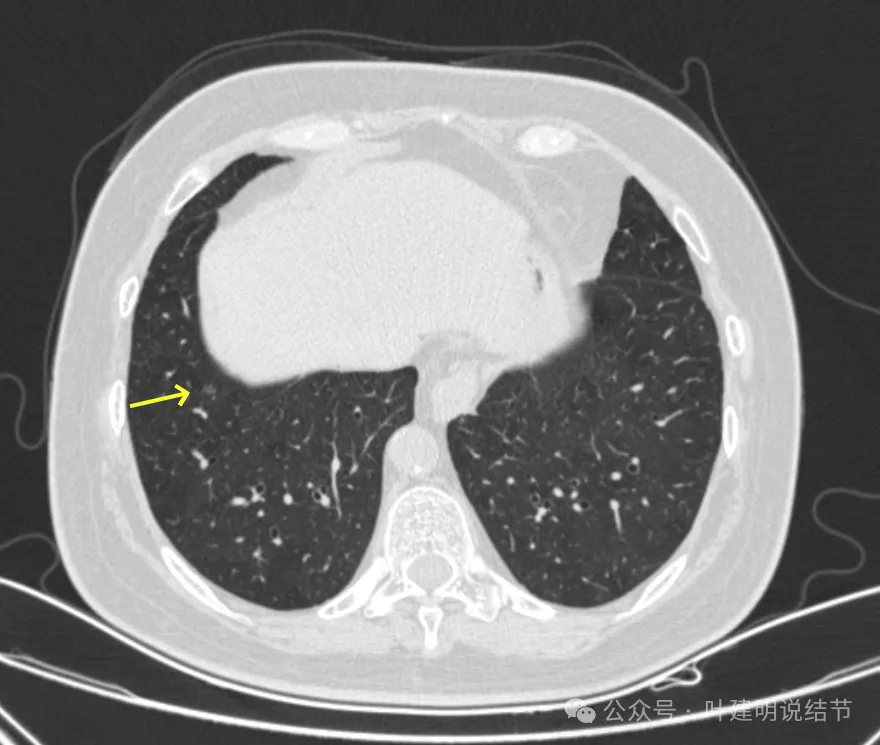

病灶1-4:两肺多处淡磨玻璃结节,密度低,散在,轮廓较清。

病灶5-6:左肺尖淡磨玻璃结节,轮廓较清。

病灶7-9:右肺上叶淡磨玻璃结节,轮廓较清。

病灶10:右侧胸膜下淡磨玻璃结节,轮廓较清。

病灶11-14:两肺淡磨玻璃结节,轮廓较清。

病灶15-18:右上叶淡磨玻璃结节,轮廓较清,有的界限稍不清。

病灶19-20:两肺淡磨玻璃结节,轮廓较清,小但边界清楚。

病灶21-22:两肺淡磨玻璃结节,轮廓较清。

病灶23-26:两肺微小淡磨玻璃结节,轮廓较清。

病灶27-30:两肺微小淡磨玻璃结节,轮廓较清。

你的两肺我数了一下,较明显的多达48处结节,还有过小的或不太确切是结节的不算,但估计在随访中仍会是结节的。大部分都是淡磨玻璃结节,轮廓与边界较为清楚,没有显著实性成分。其中最大最主要的病灶是左上叶胸膜下的,此灶轮廓清楚,磨玻璃密度,贴着胸膜,灶内密度稍不均,但未见明显异常增粗的血管进入穿行,胸膜牵拉也不厉害,考虑仍是微浸润性腺癌或浸润性腺癌贴壁为主型的阶段,近期风险仍不大,何况两肺这么多病灶,即使切了主病灶也不能解决后续其他结节进展的问题。所以个人仍倾向在风险相对可控不大的情况下,继续随访。6-9个月复查应该是安全的,其实12个月复查也不见得就会有风险。待关注最主要的病灶有风险了,再来综合评估考虑干预事宜,包括如何干预,以及处理哪几处同侧病灶。意见供参考!